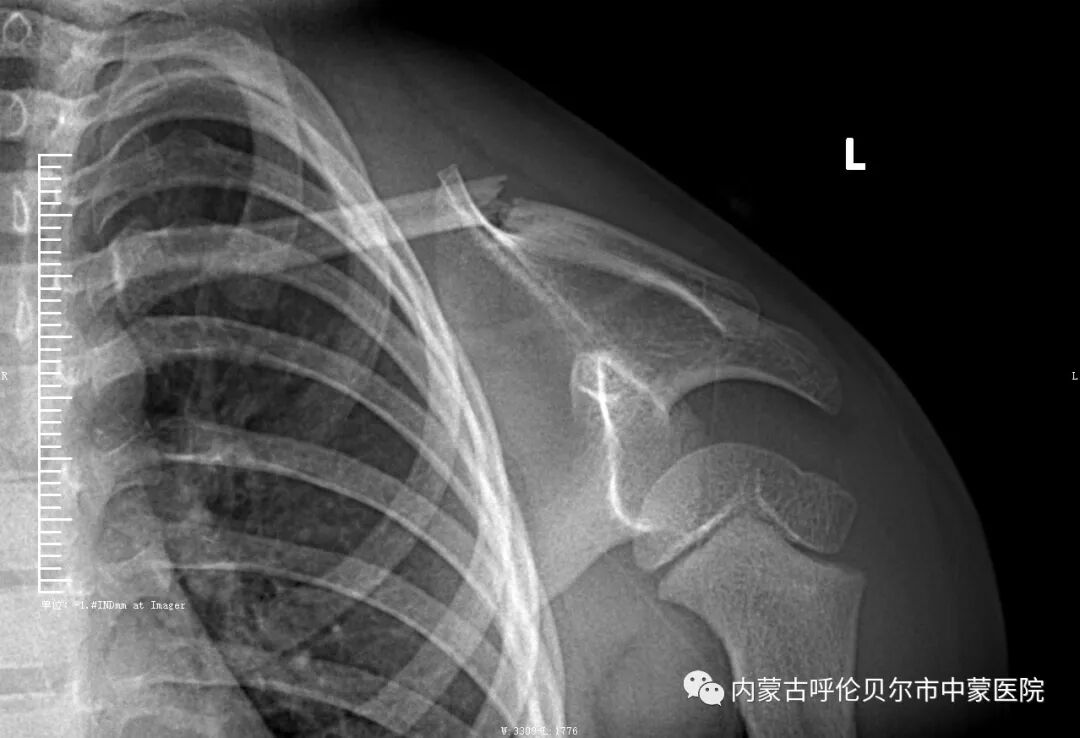

儿童1,来我院就诊前三天在家玩耍时摔伤。当时左侧肩部着地致左侧肩部疼痛、肿胀、活动受限,在家人陪同下于当地诊所捏骨治疗,但症状未见好转,遂来我院就诊,以"左侧锁骨骨折"收住院。